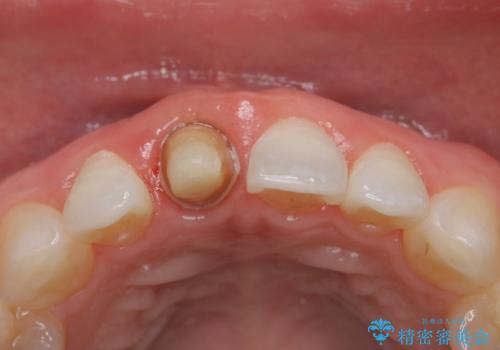

前歯の色が気になる オールセラミッククラウン(SP)

- 仮歯で矯正治療を行い、治療終了したためセラミックにて最後仕上がりをきれいにされたいという患者様の症例です。

矯正の時使用していた仮歯を新調し、その後最終的な形を作ってから型取りを行います。

色もきれいだと患者様も満足されておりました。